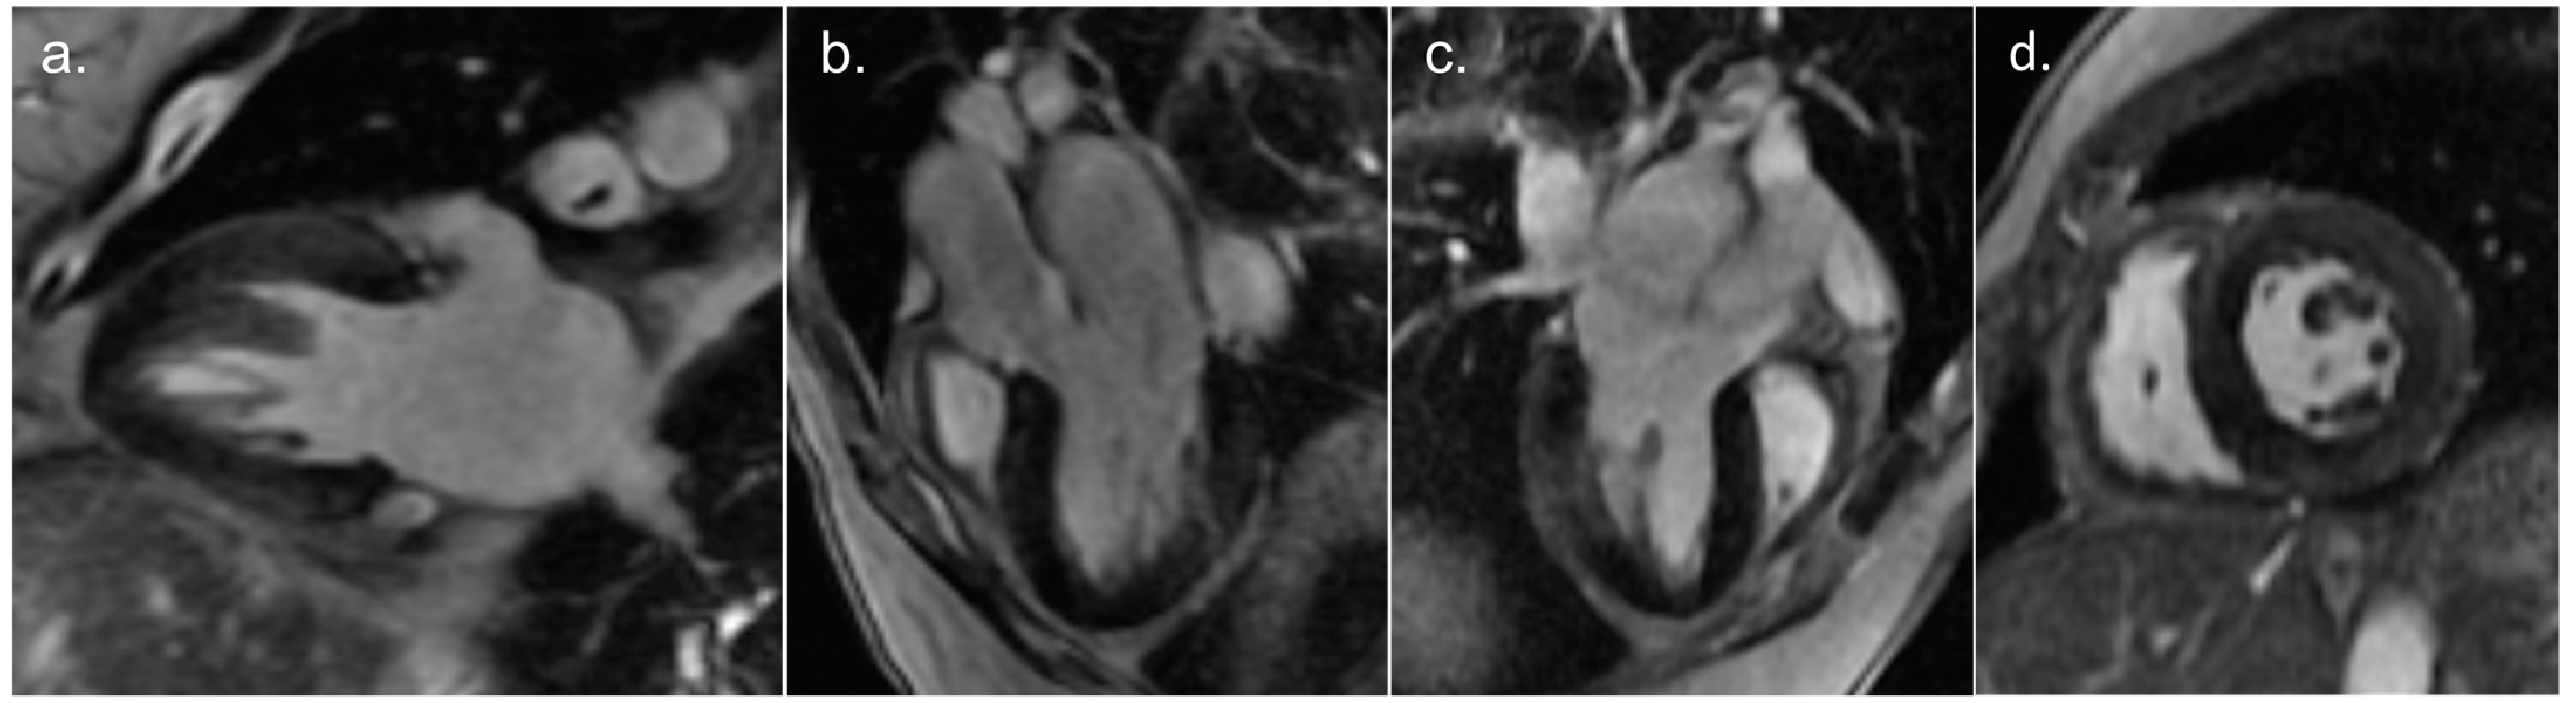

Cardiac magnetic resonance imaging (Videos S3–S6) was performed 10 days after admission, showing preserved LV function (ejection fraction 61%) with lateral wall hypokinesis and mild RV dilatation, with preserved RV function without wall motion abnormalities. Intramural and subepicardial LGE in the basal to mid segments of the inferolateral wall was noted (Figure 3). Native T1 mapping levels were slightly elevated in the myocardial region with LGE. T2 mapping levels were normal.

Figure 3.

Contrast-enhanced magnetic resonance imaging revealing intramural and subepicardial late gadolinium enhancement in the basal to mid segments of inferolateral wall. Two-chamber view (a), three-chamber view (b), modified three-chamber view (c), and mid-ventricular short axis view (d).